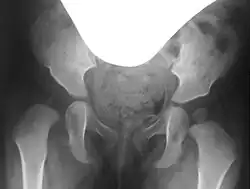

Preoperative planning involves conventional pelvic X-rays, including pelvic overview and Rippstein view images, to assess joint misalignment, severity, and surgical planning. Rippstein views provide a lateral projection of the femoral necks.[7][8]